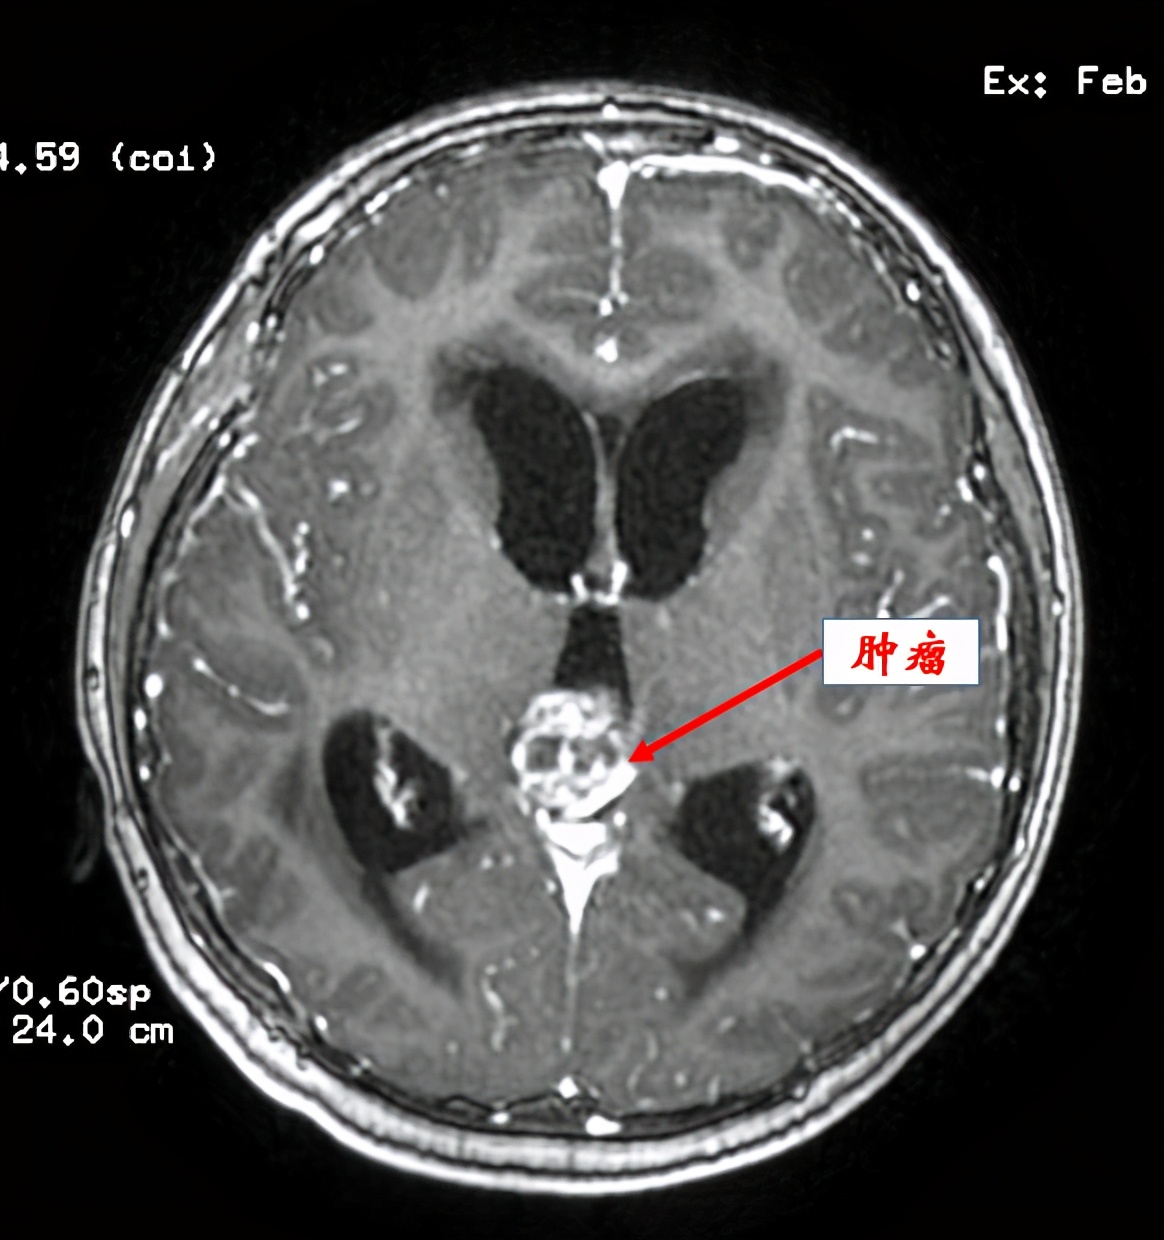

“刚来时小孩精神疲倦,不能进食,很痛苦。我们急诊给他查了CT和核磁共振,发现在颅内松果体区和第三脑室后部有一个鸽蛋大的肿瘤,而且病人出现了明显的脑积水。”陈陆馗说,民仔入院当日,我们为他行“右侧脑室钻孔引流术”,先快速解除脑积水,降低颅内高压。术后当晚,民仔精神状态较前明显改善,头痛、呕吐症状缓解,可进食流质。

图片说明:术前MRI显示松果体区及第三脑室后部肿瘤。

在做好充分术前准备之后,神经外科陈陆馗主任团队于2月22日给民仔进行了枕部开颅松果体区及第三脑室后部肿瘤切除术,肿瘤切除后,完全恢复了脑脊液循环通路,拔除了脑室引流管。病理报告显示是混合型生殖细胞肿瘤。